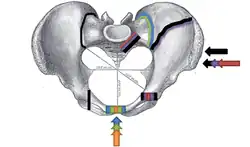

Размеры таза (в скобках у мужчин)[2]:

- Distantia interspinosa — между верхними передними подвздошными остями — 23-25 (21-23) см

- Conjugata anatomica или diameter recta (анатомическая конъюгата/прямой диаметр верхней апертуры) — между мысом крестца и верхним краем лобкового симфиза — 11,5 (10,8) см

- Diameter transversa (поперечный диаметр верхней апертуры) — наиболее отдалённое между пограничными линиями — 13,5 (12,8) см

- Diameter obliqua (косой диаметр) — между расположенными с противоположных сторон крестцово-подвздошным суставом и подвздошно-лобковым возвышением — 12,0-12,6 (12,0-12,2) см

- Прямой размер таза — между стыком II и III крестцовых позвонков и задней частью середины лобкового симфиза — 12,2 (10,8) см

- Поперечный размер таза — между центрами вертлюжных впадин — 11,5 (10,8)

- Прямой диаметр нижней апертуры — между вершиной копчика и нижним краем лобкового симфиза — 9,5 (7,5)

- Поперечный диаметр нижней апертуры — между седалищными буграми — 10,8 (8,1) см

- Угол наклона таза - угол между горизонтальной плоскостью и плоскостью верхней апертуры таза

В гинекологии и акушерстве, кроме упомянутых, имеют значение ещё следующие размеры таза[2]:

- Distantia intercristalis — между подвздошными гребнями тазовых костей — 25-27 см

- Distantia intertrochanterica — между большими вертелами бедренных костей — 28-29 см

- Conjugata vera (истинная гинекологическая конъюгата) — между мысом крестца и самой задней точкой лобкового симфиза — 10,5-11,0 см

- Conjugata diagonalis (диагональная конъюгата) — между мысом крестца и нижним краем лобкового симфиза — 12,5-13,0 см.